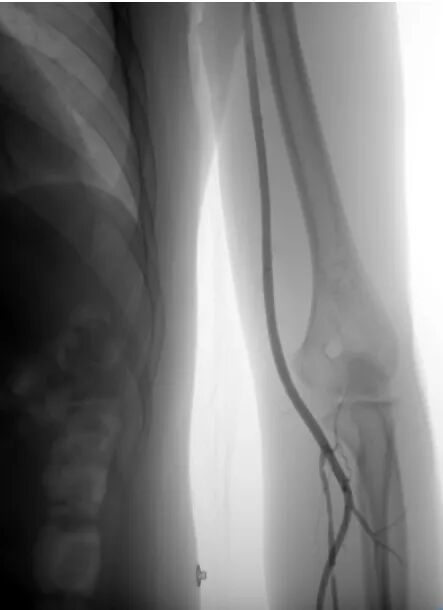

2.使用软交换导丝将头端置于降主动脉,进一步把短鞘置换成6F长鞘(适介医疗商品名:“桡鞘”),使用桡鞘配套鞘芯将桡鞘带至锁骨下动脉后撤出鞘心,再使用125MPA辅助将长鞘送到V2。

(交换过程注意事项:1、软交换导丝送到足够远,小心交换过程中通路丢失。2、桡鞘上的过程要小心抱死。)

3.考虑未一次再通需要进行二次取栓时,将桡鞘置于椎动脉V2段

4.桡鞘提供基础通路后,进一步将React中间导管到位